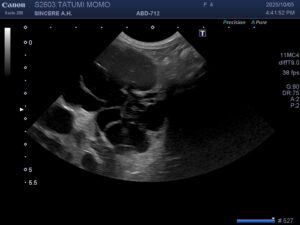

以前「多発性嚢胞腎」の診断を受けた猫さんは、その後通院点滴を続けられているのですが、当院に休診時にお世話になった別の病院の方が猫との相性が良さそうとのことで、そちらで治療をつづけられることになりました。今日は同居の猫さんの健診(ドック)においでいただきました。闘病中の猫さんのことで飼い主さんは大変心を痛めておられ、できる限りの検査を希望されました。特に「嚢胞腎」と「心筋症」を心配しておられます。当院でできるスクリーニング検査をして、結果次第では専門病院をご紹介する予定です。何件かの動物病院に通われるのは本当に大変だと思います。できるだけ猫さんと飼い主さんの気持ちに寄り添った診療をしていきたいと努めていきます。